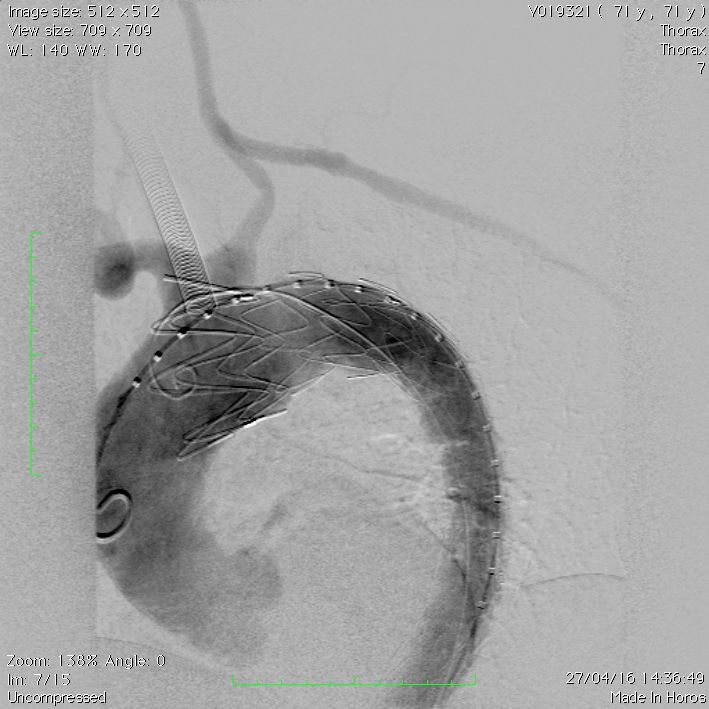

Tratamento endovascular de dissecção tipo B com debranching (ponte carotídeo-subclávia) e implante de endopróteses.

Tratamento endovascular de dissecção tipo B com debranching (ponte carotídeo-subclávia) e implante de endopróteses.